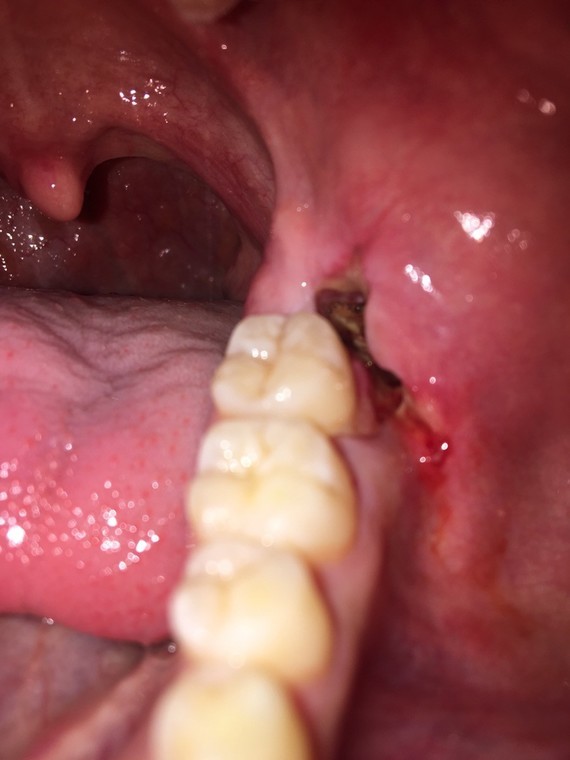

Pansement Dentaire Goût Dans La Bouche AUTOMASITES